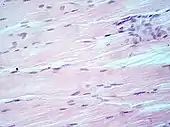

Muscle tissue, cell nuclei (blue-purple), extracellular material (pink).

H&E is the combination of two histological stains: hematoxylin and eosin. The hematoxylin stains cell nuclei blue, and eosin stains the extracellular matrix and cytoplasm pink, with other structures taking on different shades, hues, and combinations of these colors.[5][6] The stain shows the general layout and distribution of cells and provides a general overview of a tissue sample's structure.[7] Hence a pathologist can easily differentiate between the nuclear and cytoplasmic parts of a cell.

Hematoxylin principally colors the nuclei of cells blue or dark-purple,[6][15][14] along with a few other tissues, such as keratohyalin granules and calcified material. Eosin stains the cytoplasm and some other structures including extracellular matrix such as collagen[5][7][14] in up to five shades of pink.[8] The eosinophilic (substances that are stained by eosin)[5] structures are generally composed of intracellular or extracellular proteins. The Lewy bodies and Mallory bodies are examples of eosinophilic structures. Most of the cytoplasm is eosinophilic and is rendered pink.[10][15] Red blood cells are stained intensely red.